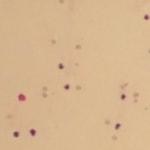

関節液検査により診断することができます。罹患動物の関節液は、正常な関節液と比較して、粘稠度の低下や顕微鏡下にて非変性性好中球の増加が認められます。

症例2:パピヨン 11歳 去勢雄

移動性跛行、食欲・活動性の低下を主訴に来院。発熱、手根関節の腫脹および関節痛が認められた。血液検査を行ったところ白血球数の上昇が認められた。関節液検査にて細菌や貪食像は認められず、非変性性好中球が多数採取された。免疫介在性関節炎を疑い、免疫抑制剤の投与を開始した。プレドニゾロンを1日1回1.8mg/kgでスタートするが、改善は認められず、プレドニゾロンを1日2回1.8mg/kgと増量したところ一般状態は改善し、跛行や発熱は認められなかった。今後、定期的な血液検査と体温測定を行い、他の免疫抑制剤の併用することでステロイドの減量を図ると同時に、副作用の有無を確認していくこととしている。